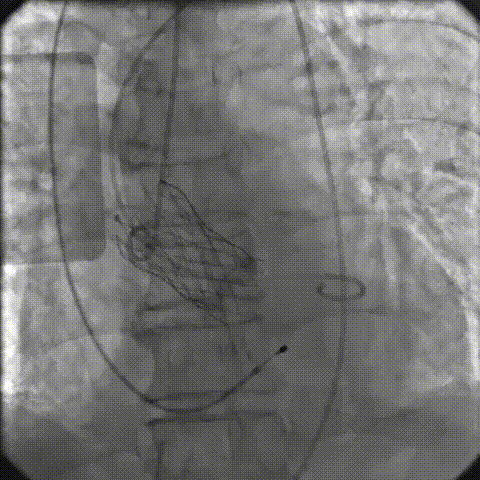

手术影像记录

主动脉根部造影

18mm球囊预扩

零位定位逐步释放至工作位,多角度评估位置良好

缓慢脱钩至完全释放,最终植入位置理想